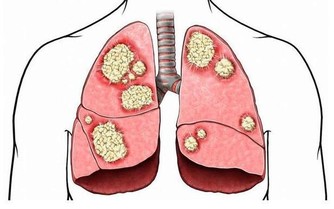

糖尿病患者由於存在代謝紊亂,加上血糖高、排尿多,以及糖尿病對微血管及末梢神經的損害,他們的皮膚黏膜常處於慢性脫水、缺氧和營養不良的狀態,比普通人體表更乾燥、彈性減退、表皮纖薄,再生能力與抗感染的屏障作用均降低,故易患多種皮膚病並不奇怪。如果皮膚瘙癢反復不愈應及時讓內分泌科醫生排除糖尿病可能。

臨床上糖尿病患者常見的皮膚病有:

化膿性感染:主要為金黃色葡萄球菌、鏈球菌等感染毛囊引起的癤、癰,此病會此起彼伏反復發作,如果一味地治皮膚病,忽視血糖的控制,極易發展為敗血症而危及生命。

真菌感染:有毛癬菌所致的股癬、甲癬、足癬和手癬;有念珠球菌所致的口炎、陰道炎、巴氏腺炎,同樣也是好好壞壞難以根治。

皮膚瘙癢症:包括全身性瘙癢和局限性瘙癢,其中女性外陰瘙癢比較多見。皮膚會因搔癢而不斷搔抓造成皮膚佈滿抓痕、血痂,最終導致苔蘚化。

脛前色素斑:病程超過五年的患者,小腿前側可有園形或橢圓形萎縮性淡棕色斑,系毛細血管破裂、含鐵血紅蛋白沉積而成。男性多於女性。

糖尿病足:高血糖導致下肢血管、神經系統病變,一旦皮膚稍有破損、感染而不及時感知或治療,將會迅速形成潰瘍、壞疽,最終不得不做截肢處理,造成病人身體上、心理上雙重打擊,生活質量大大下降,嚴重的甚至還會危及生命。

糖尿病性水皰病:見於久病且血糖控制不佳的患者,特徵是肢體末端表皮有大小不等的透明水皰,內含清亮漿液,酷似燙傷水皰,會自行消失,但若磨擦則可能繼發感染。

其他在臨床上偶見的還有:糖尿病性類脂質漸進性壞死、糖尿病性黃色瘤、毛細血管脆性增加性紅斑、紫癜、硬化性皮膚水腫等。